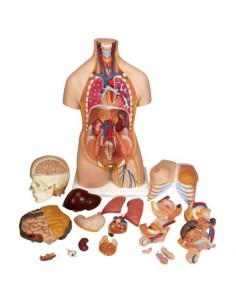

Scopri il Mondo dell’Anatomia con Modelli anatomici di Precisione

Benvenuto su Tuttoanatomia.it, il portale di riferimento in Italia per l’acquisto di modelli anatomici, poster, lettini portatili, simulatori medici e letteratura specialistica. Con i nostri modelli anatomici di 3B Scientific ed Erler Zimmer, leader mondiali nel settore, offriamo un’esperienza di apprendimento senza pari.

Modelli Anatomici Dettagliati per Ogni Necessità

Dal cranio in 22 parti con incastri magnetici ai modelli di colonna vertebrale, da quelli di articolazioni a quelli di cuore, ogni pezzo della nostra collezione è progettato per un’immersione totale nello studio dell’anatomia umana. I nostri modelli, realizzati tramite scansioni di ossa vere, garantiscono un’esperienza tattile autentica e una fedeltà di peso quasi identica agli originali.

Strumenti Didattici Innovativi per l’Educazione e la Pratica Medica

Essenziali per studenti e professionisti, i nostri modelli anatomici sono strumenti didattici che permettono di osservare le strutture anatomiche con precisione, eliminando la necessità di dissezioni o studi invasivi. Sono inoltre utili per spiegare ai pazienti le patologie, rendendo la comunicazione più efficace e risparmiando tempo prezioso.